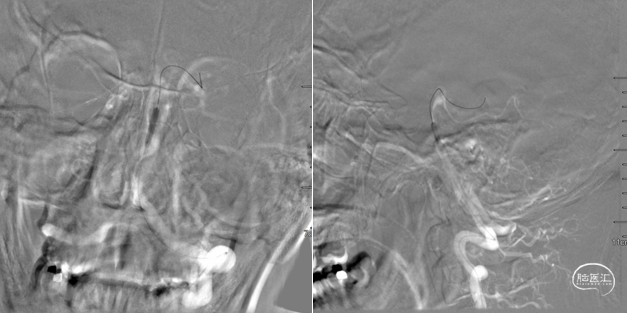

术前造影,BA近端闭塞。

术前造影,LC7次全闭塞。

术前造影,RICA 通过交通动脉向左侧颈内动脉及基底动脉尖代偿供血。

微导管造影。

支架释放后发现远段大负荷血栓影,近端狭窄,狭窄不解除,远端血栓很难清除。

碎屑栓子取出,近端狭窄影响远端栓子清除,拟近端球扩,取栓后有小缝隙,留个路图,方便导丝通过。